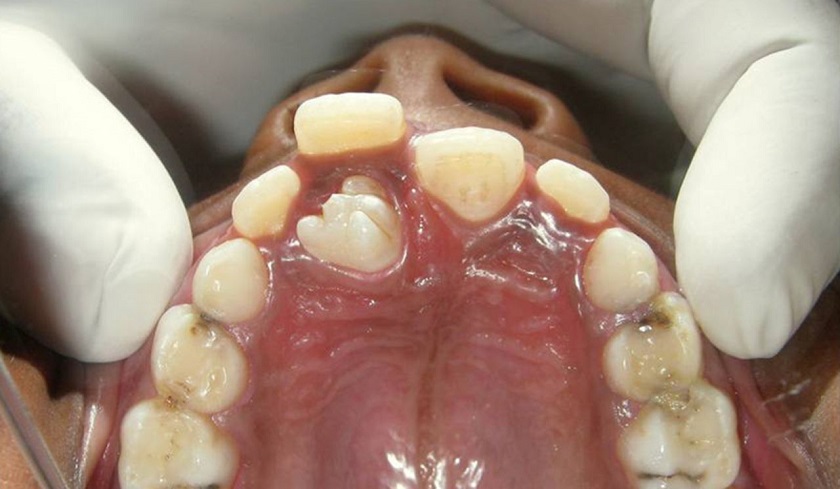

Răng thừa có thể xuất hiện ở bất kì vị trí nào, hình thành nên nhiều kẽ hở khiến thức ăn dễ mắc vào, tạo điều kiện cho vi khuẩn có hại tác động trực tiếp đến răng nướu, dễ phát sinh các bệnh lý răng miệng, ảnh hưởng đến các răng xung quanh.

Răng mọc thừa phổ biến nhất là ở gần vị trí răng vĩnh viễn và răng cửa trước hàm trên. Vị trí các răng thừa mọc nhiều thứ hai chính là bốn chiếc răng hàm.